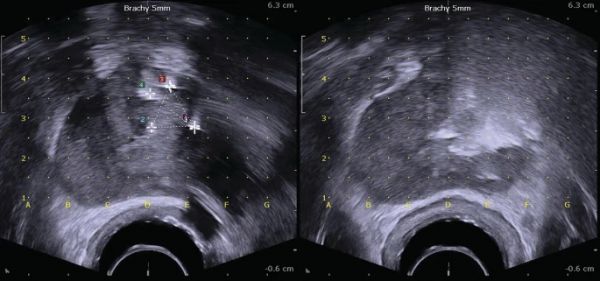

插入超声的扩展截石位置 为了确定治疗区域,使用配备腔内探头的双平面 TRUS 系统在矢状和轴向上对前列腺进行可视化。必须确定前列腺的体积和形状,并将数据输入规划软件系统。19 号单极电极针在连续超声引导下使用近距离放射治疗网格经会阴插入(图 16.3 )。 图 16.3

在连续超声引导下使用近距离放射治疗网格经会阴插入 19 号单极电极针

测量治疗前的超声图像(左)、针到位和相对距离;治疗后(右)超声显示伪影主要是高压电流产生的电泳气体